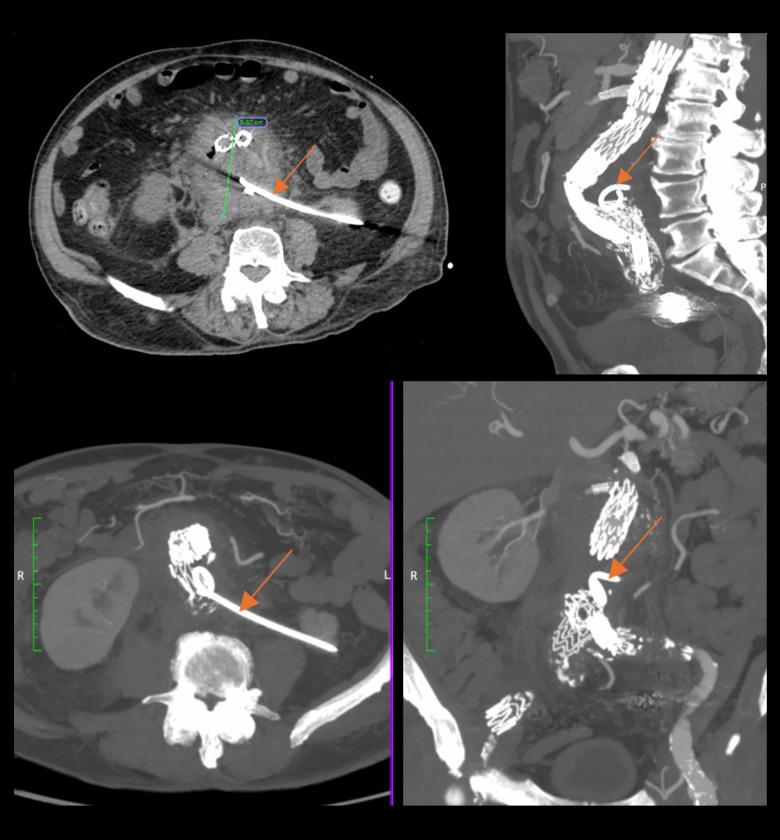

BACKGROUND Aorto-duodenal fistula (ADF) is a communication between the aorta and the duodenum and requires urgent aortic repair. However, it often leads to life-threatening complications. Thus, an early and appropriate diagnostic method is necessary to deliver adequate treatment. This report describes the case of a 68-year-old man with anaorto-duodenal fistula following emergency endovascular repair of a 14-cm abdominal aortic aneurysm (AAA) identified using oral contrast computed tomography (CT), and discusses the consequences of delayed treatment and ADF management. CASE REPORT We present a case of a 68-year-old White man with abdominal bloating, who upon further examination was diagnosed with an AAA, which was successfully treated by endovascular aneurysm repair (EVAR). However, 1 year later, an endoleak was discovered and, despite the physicians' efforts, the overall treatment was complicated due to the patient's continuous postponement of treatment over several years. The aneurysm continued to expand until it reached 14 cm. Despite the successful endovascular repair of the endoleak, a duodeno-aortic fistula (DAF) was diagnosed using CT with oral contrast. The patient was managed conservatively with aneurysmal sac drainage and antibiotic therapy, which decreased the size of the aneurysmal sac. Despite early diagnostic efforts and interventions, the patient's condition deteriorated due to further complications, ultimately resulting in death. CONCLUSIONS This case report demonstrates a potential useful diagnostic role of CT with oral contrast in detecting DAF, in situations when other methods fail to do so, and emphasizes the importance of prompt intervention to prevent life-threatening complications. However, further investigations to explore the underlying mechanism and its replicability are required.

背景 主动脉十二指肠瘘(ADF)是主动脉与十二指肠之间的连通,需要紧急进行主动脉修复。然而,它常常导致危及生命的并发症。因此,需要一种早期且合适的诊断方法来进行充分治疗。本报告描述了一例68岁男性患者,在使用口服对比剂计算机断层扫描(CT)确诊为14厘米腹主动脉瘤(AAA)并进行紧急血管内修复后发生主动脉十二指肠瘘的病例,并讨论了延迟治疗的后果及ADF的处理。病例报告 我们报告一例68岁白人男性患者,有腹部胀满症状,进一步检查诊断为AAA,通过血管内动脉瘤修复术(EVAR)成功治疗。然而,1年后发现内漏,尽管医生努力,但由于患者多年来持续推迟治疗,整体治疗变得复杂。动脉瘤持续扩大直至达到14厘米。尽管成功进行了内漏的血管内修复,但通过口服对比剂CT诊断出十二指肠主动脉瘘(DAF)。患者接受了动脉瘤囊引流和抗生素治疗的保守治疗,这减小了动脉瘤囊的大小。尽管进行了早期诊断和干预,但由于进一步的并发症,患者病情恶化,最终导致死亡。结论 本病例报告表明,在其他方法无法检测到DAF的情况下,口服对比剂CT在检测DAF方面具有潜在的有用诊断作用,并强调了及时干预以预防危及生命并发症的重要性。然而,需要进一步研究以探索其潜在机制及其可重复性。